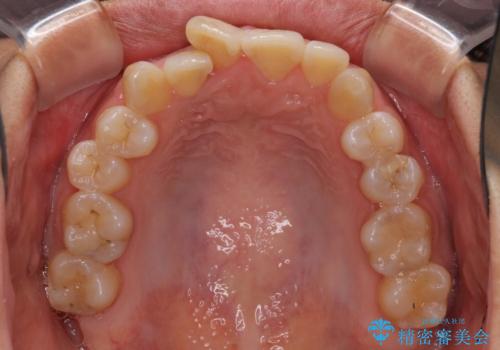

前歯のデコボコをインビザラインでスッキリと仕上げる

- 上下前歯のデコボコと奥歯の銀歯を気にして来院された患者様です。

口元をインビザラインにより歯列を整え、その後に失活している奥歯をオールセラミッククラウンにて補綴治療することとしました。

長時間のマウスピース装着に協力いただき、自然な口元に仕上げることができました。

気になっていた銀歯もオールセラミッククラウンで本物の歯のようになり、患者様には大変満足していただきました。